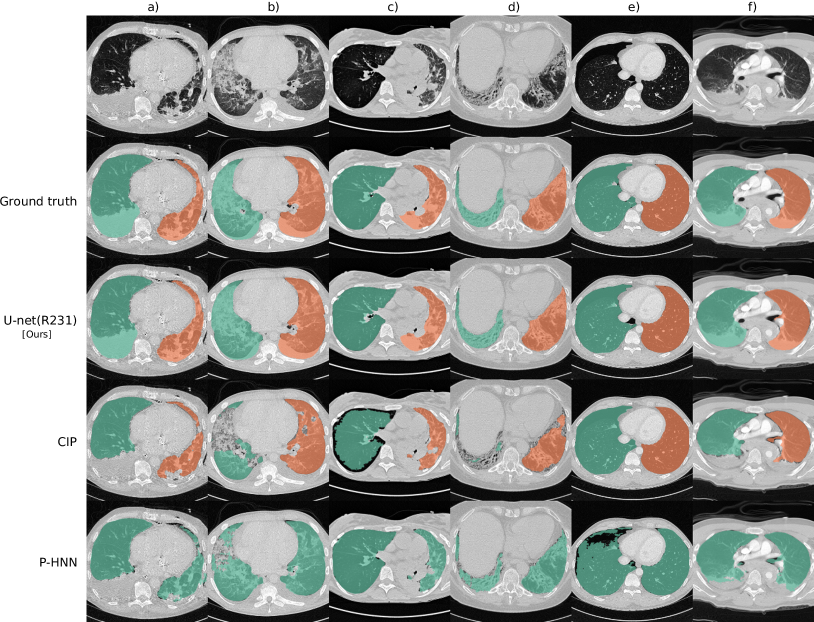

Models trained on routine data achieve improved evaluation scores compared to models trained on publicly available study data. U-net, ResU-net, and Deeplab v3+ models, when trained on routine data (R-36), yielded the best evaluation scores on the merged test dataset (All, n = 62). The U-net yields mean DSC, HD95, and MSD scores of 0.96 0.08, 9.19 18.15, 1.43 2.26 when trained on R-36 [U-net(R-36)] and 0.92 0.14, 13.04 19.04, 2.05 3.08 when trained on VISC-36 (R-36 versus VISC-36, p = 0.001, 0.046, 0.007) or 0.94 0.13, 11.09 22.9, 2.24 5.99 when trained on LTRC-36 (R-36 versus LTRC-36, p = 0.024, 0.174, 0.112). This advantage of routine data for training is also reflected in results using other combinations of model architecture and training data. Table III lists the evaluation results in detail. We determined that the influence of model architecture is marginal compared to the influence of training data. Specifically, the mean DSC does not vary for more than 0.02 when the same combination of training and test set was used for different architectures (Table III). Compared to readily available trained P-HNN model, the U-net trained on the R-231 routine dataset [U-net(R-231)] yielded mean DSC, HD95, and MSD scores of 0.98 0.03, 3.14 7.4, 0.62 0.93 versus 0.94 0.12, 16.8 36.57, 2.59 5.96 (p = 0.024, 0.004, 0.011) merged test dataset (All, n = 62). For comparison with the CIP-algorithm, only volumes for which the algorithm did not fail were considered. On the merged dataset (All, N=62) the algorithms yielded mean DSC, HD95, and MSD scores of 0.98 0.01 ,1.44 1.09 ,0.35 0.19 for the U-net(R213) compared to 0.96 0.05, 4.65 6.45, 0.91 1.09 for CIP (p = 0.001, 0.001, 0.001). Detailed results are given in Table IV. Fig. 2 shows qualitative results for cases from the routine test sets and Fig. 3 shows cases for which the masks generated by the U-net(R-231) model yielded low DSCs when compared to the ground truth. We created segmentations for the 55 cases of the LOLA11 challenge with the U-net(R-231) model. The unaltered masks yielded a mean overlap score of 0.968 and with dense areas removed 0.977. Table V and Fig. 4 show results for tumour overlap on the 318 volumes of the Lung1 dataset. U-net(R-231) covered more tumour volume mean/median compared to P-HNN (60%/69% versus 50%/44%, p 0.001) and CIP (34%/13%). Qualitative results for tumour cases for U-net(R-231) and P-HNN are show in Figs. 5b, c. We found that 23 cases of the Lung1 dataset had corrupted ground-truth annotation of the tumours (Fig. 5d). Fig. 5e shows cases with little or no tumour overlap achieved by U-net(R-231).